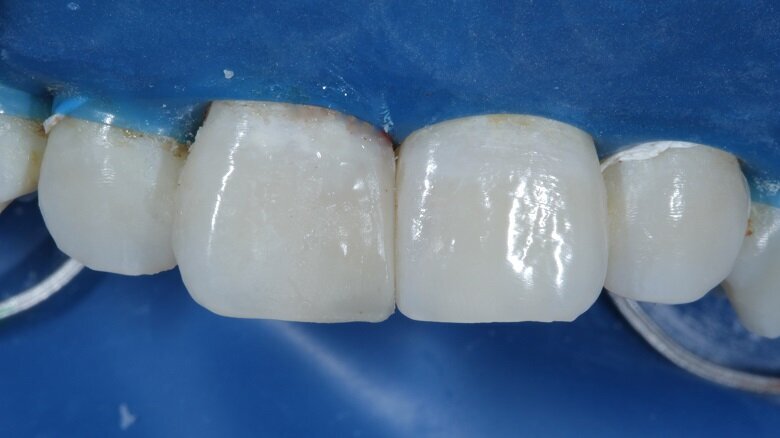

The shades that were selected were A2 Dentin, A2 Body and A2 Enamel. After this, isolation was achieved with a rubber dam (Fig 6). The caries of both 11 and 21 were excavated using a small round carbide bur (Fig 7). Primary and secondary bevels were given on tooth no 11 (Fig 8). After re-evaluation of the mesio-distal width of both the incisors, slight enameloplasty was done on tooth no 21 (Fig 9).

Fig 6: Isolation under a rubber dam